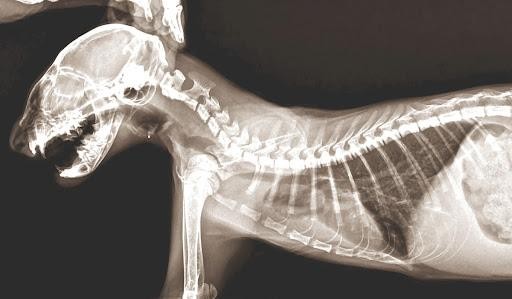

Специальная клиническая диагностика – это использование инструментов и лабораторных исследований. Для постановки диагноза может использоваться рентген, УЗИ, анализы крови и многое другое.